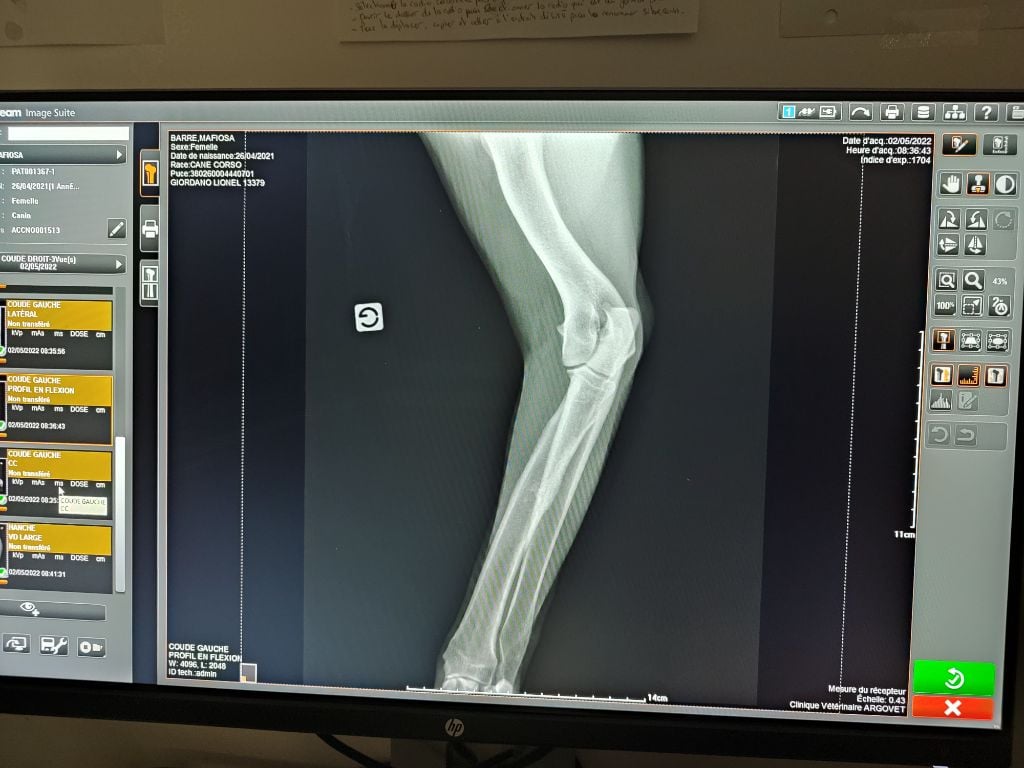

| Couleur | noire ADN HD C / ED 0/ DSRA N/N |